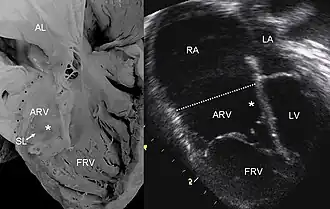

Pathological specimen and ultrasound image of a heart with Ebstein anomaly. Abbreviations: RA: Right atrium; ARV: Atrialized right ventricle; FRV: Functional right ventricle; AL: Anterior leaflet; SL: Septal leaflet; LA: Left atrium; LV: Left ventricle; asterisk: grade II tethering of the tricuspid septal leaflet.